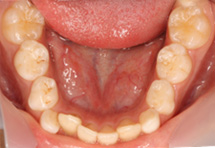

3、臼歯交叉咬合(すれ違い咬合)

・乳歯列期から治療を開始することをおすすめします。

指しゃぶりや口呼吸などによって上顎の歯列が通常に比べて狭くなっている場合、臼歯部の交叉咬合(すれ違い咬合)を引き起こすことがあります。

特に、上下正中線(前歯の真ん中のライン)が顔の真ん中のラインからずれていたり、顎が側方に偏って曲がったようになっている状態の交差咬合の場合、自然に治ることはありません。

骨格性の下顎前突と同じように、成長とともに下顎がさらに偏った状態で発育し、放っておいても症状はどんどん悪化していってしまいます。

そしてそのような交叉咬合は、歯列の変形や顎の不均衡な発育などから顔の変形(非対称)をきたし、将来、顎関節症や顎機能異常の原因となる可能性があります。

乳歯列期は上顎歯列を拡大して正常な顎やお口周りの筋肉の成長発育を促す良い時期でもありますので、この時期に治療をされることが望ましいとされています。

上顎急速拡大を3回行い鼻腔通気が改善しました。

咀嚼指導により、正中が合い、咬み合わせが安定しています。